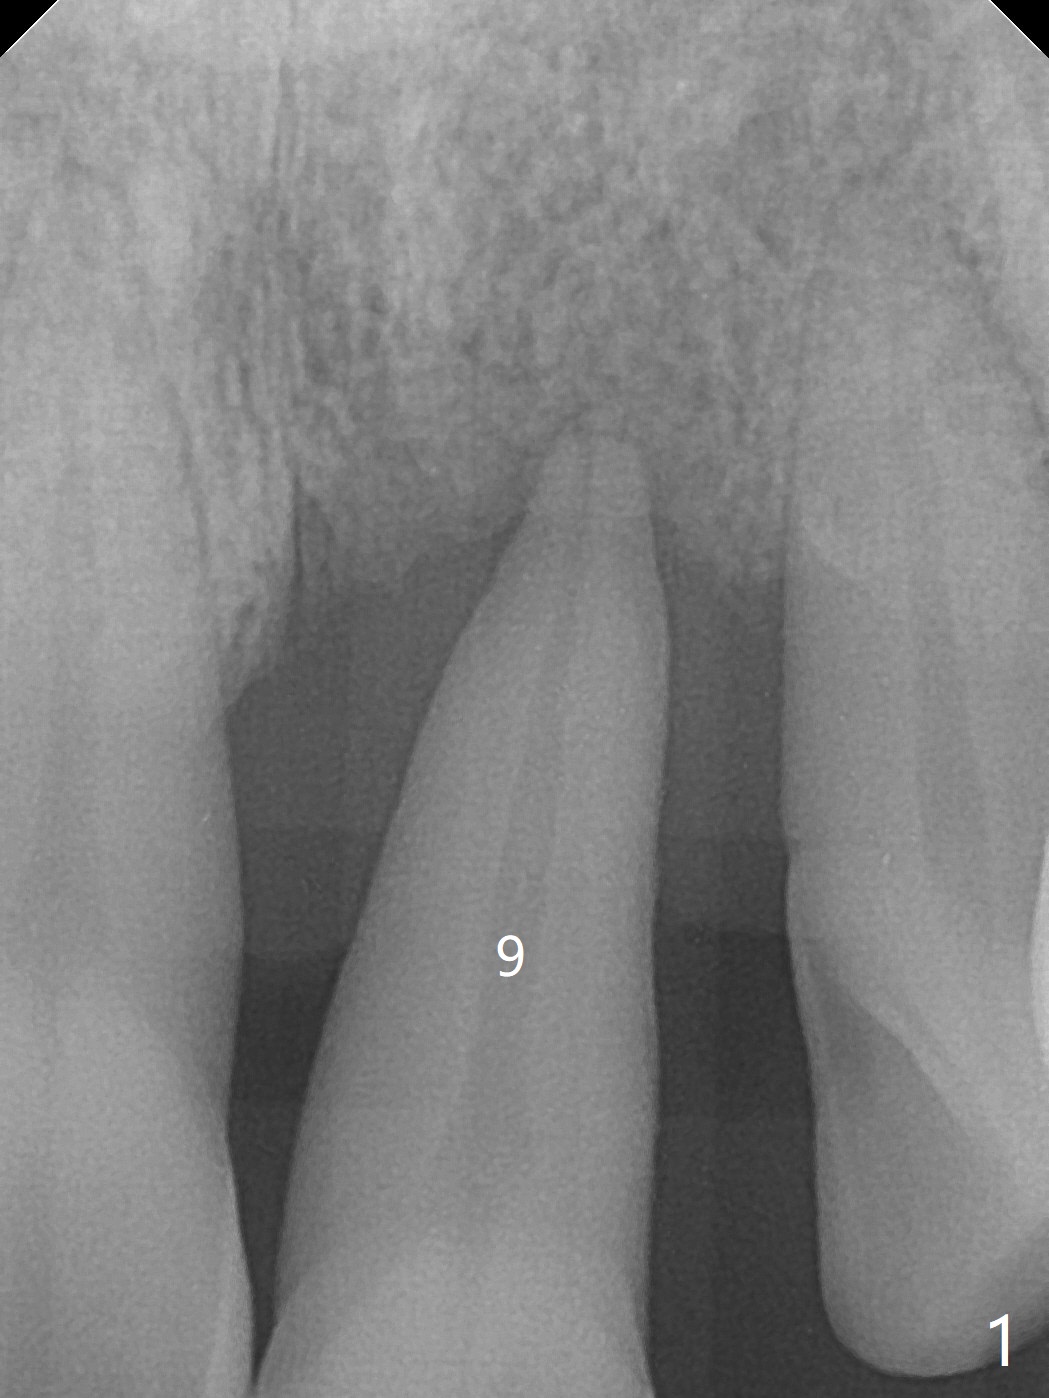

A 67-year-old man requests extraction of the loose tooth #9 (Fig.1). After extraction, the labial plate is found to be missing. With incision, allograft is kept in place with a 12x24 mm anterior narrow Cytoplast and 4-0 Chromic gut suture (Fig.2). Periodontal dressing dislodges in 2 days. The wound dehisces transversely 5 days postop (Fig.3 arrows), whereas the wound was open buccopalatal when the sutures were placed. Probably due to extensive dissection, the erythematous mucosa is large (Fig.4), although asymptomatic. When X-ray shows V-shaped bony defect (Fig.1 (PA), 5 (Pan), 6 (CT)), do not dissect the overlying thin buccal gingiva, which is most likely to dehisce. In fact immediate implant with guide appears to be more conservative, since there is no pressure against the buccal gingiva (Fig.7,8). To be more ideally, the implant could be placed more coronally, longer (13 mm instead of 11.5, Fig.9,10) and narrower (3.5 mm instead of 4.0 mm, Fig.11 (red circles: bone graft)).